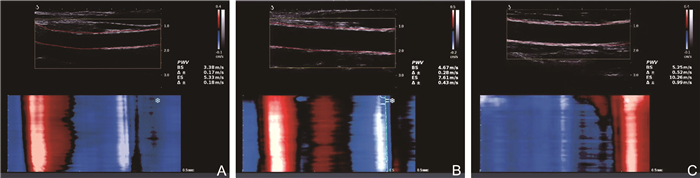

• 图  1  SLE组与健康对照组ufPWV技术检查结果

注:A为对照组,PWV-BS为3.38 m/s,PWV-ES为5.33 m/s;B为轻度活动组,PWV-BS为4.67 m/s,PWV-ES为7.61 m/s;C为中重度活动组,PWV-BS为5.25 m/s,PWV-ES为10.26 m/s。

Figure  1.  Results of ufPWV technique examination in the SLE group and healthy control group